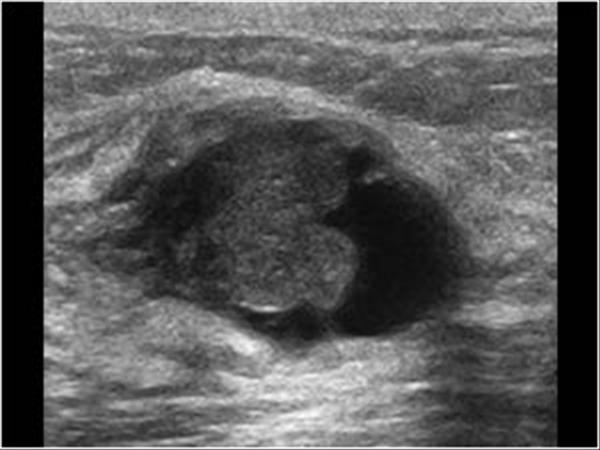

Kista payudara yang kompleks yang mengandung campuran jaringan padat di dalam kista payudara mungkin memiliki risiko perubahan ganas, oleh karena itu perlu diselidiki dan dipantau.

Kista payudara yang kompleks

Skrining payudara secara teratur dengan MMG dan USG payudara untuk menyingkirkan benjolan kanker yang mencurigakan